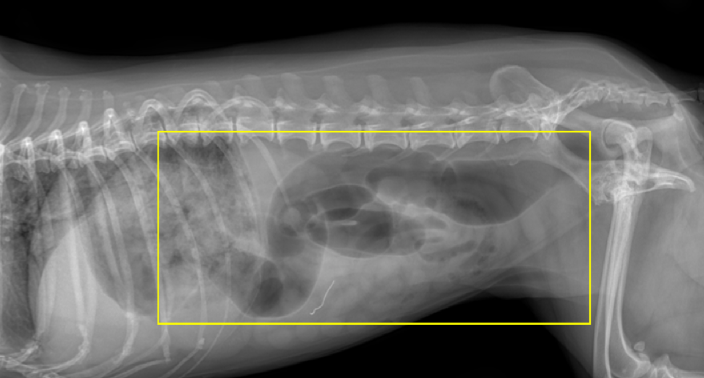

또한, x-ray상에서 위의 내용물이 다량 저류, 소장 확장이 동반된 상태였습니다.

그림 2. 확장된 소장 분절